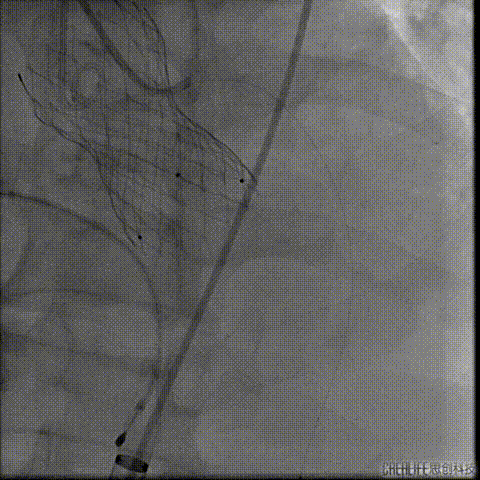

行急诊手术 腹主动脉及左侧股动脉造影

左侧股动脉见造影剂外渗

球囊压迫后植入覆膜支架

复查造影